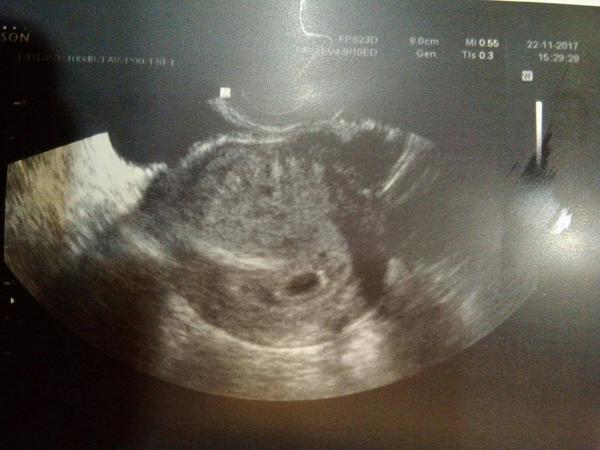

Vzhledem k tomu,ze jsem nenašla žádnou novější diskuzi,tak zakládám znovu.....Představte si co se mi stalo.Jeste den pred očekávanou MS jsem si udělala test a //.Super!Naběhla jsem dle instrukci hned k Dr.( v listopadu jsem totiz prodelala zamlkly potrat a revizi☹ ).Dr.potvrdila 4+2 a gestační váček na UZ a pozvala za tyden na kontrolu.Jenže za pět dní jsem začala spinit a krvacet,na pohotovosti měli co dělat aby na UZ vůbec něco viděli.Tak jsem dostala Agolutin a mazala zase dom.Pak celou neděli jsem byla jak pribita k posteli abych do pondělní kontroly vydržela.K doktorce jsem šla uz smířena se vším......Ta mi ale vyrazila dech.Na UZ byly nyni dva gestační váčky!Jeden odpovídající 7tt(bohužel bez ❤),a druhy odpovídající 5tt- ten snad bude OK.Takže nejspíš syndrom mizejícího dvojčete.Tak teď každý den přemlouvám toho bobka ať to vybojuje.....No ale jak je to možný otěhotnět ve dvou cyklech....jsem z toho jelen......Mate někdo podobnou zkušenost??

I já mám indikovan syndrom mizejícího dvojcete. U mě to na začátku tehu vypadalo na mimodelozni, pak mi v nemocnici potvrdili jeden plod a o týden později mě má gyn překvapila také tím, že čekám dvojvajecne dvojčata. Jedno bylo asi o týden starší a také větší. Druhé mimi mělo podstatně menší dutinku, kde se vyvíjelo. V cca 10 týdnu bohužel tomu menšímu přestalo tlouct srdíčko. Mudr mě na to trochu připravovala, vzhledem k jeho podmínkám ☹. Nic se s tím nedělá, samo se to vstřebá. Časový rozdíl bývá mezi dvojčaty běžný.. Teď jsem v 17+5 a čekáme chlapečka. Příroda je hold někdy mocnější...

Jako jsi zezule psala ty, tak v den neMS jsem našla //. V 5+4tt jsem byla na prvním vyšetření a byl tam gestační váček, možná i plod a doma jsem si na fotce všimla i bublinky nad tím.

Na další kontrole jsem byla v 7+2tt a oba drobečci dost vyrostli. O srdíčkách mi nic neřekl, takže netuším. Když jsem se sama zeptala, co je to to druhé, tak mi akorát sdělil, že asi mizející dvojče. Ale nechápu, kde k tomu takhle přišel. Vždyť náramně vrostlo a nijak se o to ani nezajímal mi přišlo. Na další kontrolu jsem objednaná až 8.1. (po pěti týdnech) a už pomalu 4 týdny tohle řeším a nedá mi to spát :/